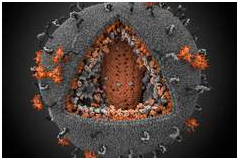

- بیماری ایدز: در سال 2009 گزارش شد که 33 میلیون نفر از مردم جهان با این بیماری زندگی می کنند و طبق گزارش سازمان بهداشت جهانی 1.8 از این جمعیت جان خود را به دلیل ابتلا به این بیماری از دست دادند.